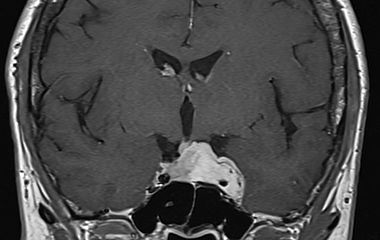

Die komplexe Anatomie und Nähe zu lebenswichtigen Strukturen sowie den wichtigen Steuerungszentralen der Hormone machen Erkrankungen der Schädelbasis stellen besondere Anforderungen an Diagnostik und Therapie. Als Teil des interdisziplinären zertifizierten Schädelbasiszentrums am Uniklinikum Augsburg besitzt die Klinik für Neurochirurgie eine große Expertise im gesamten Spektrum der operativen Therapie an der Schädelbasis. Dazu gehören Schädelbasistumoren wie Meningeome, Schwannome (Vestibularisschwannome), Hypophysentumore, Vaskuläre Dekompression bei Gefäß-Nervenkonflikten (Trigeminusneuralgie) sowie die Versorgung komplexer Schädelbasisfrakturen.

Hypophysentumore

Die Behandlung von Pathologien erfordert Erfahrung, Präzision, interdisziplinäre Zusammenarbeit mit den Kliniken für Hals-Nasen-Ohrenheilkunde, Neuroradiologie, Endokrinologie und Strahlentherapie. Oberstes Ziel ist die Sicherheit der Patientinnen und Patienten. Dazu gehört auch zu wissen, wann man nicht weiter gehen kann. Wir nutzen die neueste Technik um diese Ziele zu erreichen. So führen wir unsere Operationen mikrochirurgisch oder unter Zuhilfenahme eines Endoskops durch. Die Planung erfolgt bereits vor der Operation und kann mittels Neuronavigation wie geplant durchgeführt werden. Zur Schonung der Nerven und wichtiger Strukturen setzen wir routinemäßig das intraoperative Neuromonitoring ein um in Echtzeit während der Operation drohende Schädigungen zu erkennen und zu vermeiden.